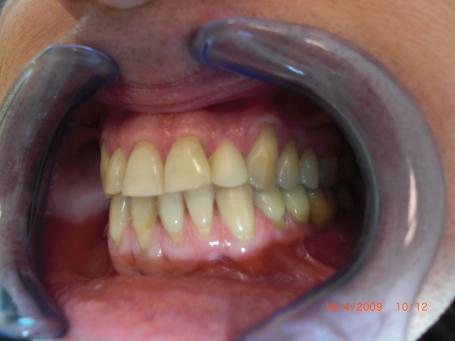

3°)Couronne provisoire en résine.

La couronne provisoire est placée pour maintenir la gencive à distance des limites de la future couronne et de préserver l'esthétique durant la fabrication de la couronne définitive. Cette couronne est scellée avec un ciment provisoire.